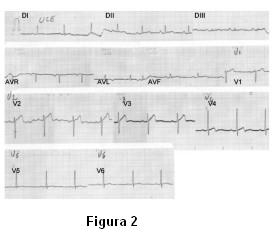

Se interpreta el cuadro como pericarditis aguda y se inicia tratamiento con analgésicos no esteroideos. El paciente refiere mejoría progresiva de los síntomas aliviando completamente a las tres horas del ingreso. Evoluciona asintomático por 48 horas. Se realizan ECG seriados donde se evidencia disminución del supradesnivel del segmento ST y de la amplitud de las ondas T presentes en los ECG previos (figura 2).